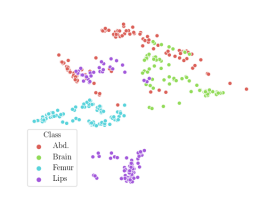

We compare the -distance of categorical features and domain features. Fig. 5 (a) shows that domain difference is higher in domain features than in categorical features. This indicates that domain features contain more domain information whereas categorical features are more domain-invariant. Fig. 6 shows the t-SNE plot of categorical features in both domains for MIDNet. From Fig. 6 (a), we observe that the categorical features learned by MIDNet enable the anatomical classification. Fig. 6 (b) shows that the learned categorical features are domain-invariant.

In addition, we utilize t-SNE plots for feature visualization in Fig. 10. Comparing Fig. 10 (a) and Fig. 10 (b), we observe that with mutual information disentanglement, (1) samples from the same category are more tightly clustered (see the top row) and (2) the source domain and the target domain are overlap more (see the bottom row). This indicates that mutual information disentanglement is important for learning categorical-focused and domain-invariant features. Fig. 10 (a), (c)-(d) show that the proposed method outperforms other state-of-the-art methods for learning category-discriminative and domain-invariant features, especially for unseen categories in the target domain (e.g., (a) vs. (d)).